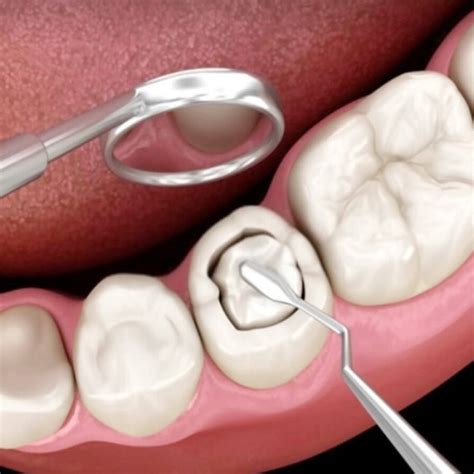

Para la obturación directa se sigue este procedimiento:

- Evaluación y diagnóstico: Lo primero que hace el dentista es evaluar el caso del paciente y hacer un diagnóstico. Así determina si es necesario aplicar obturación en uno o varios dientes.

- Anestesia: Luego de saber que lo necesitas es una obturación dental, el procedimiento comienza con la aplicación de la anestesia, para adormecer el área y evitar el dolor. En este tratamiento se requiere de anestesia local, que se coloca en la zona del diente dañado. El primer paso en el procedimiento es la aplicación de anestesia local. Este tratamiento busca minimizar cualquier posible malestar durante la intervención. La anestesia se inyecta en la encía o alrededor del diente afectado, asegurando que el paciente no sienta dolor mientras se llevan a cabo los siguientes pasos.

- Preparación del diente y eliminación de caries: Para continuar, con un taladro dental, se procede a la eliminación de las caries. Esto hará que queden unos pequeños agujeros o cavidades que deben limpiarse muy bien, para evitar que la infección pueda extenderse. Una vez que la anestesia ha hecho efecto, se procede a la eliminación de la caries. Con un instrumento dental especializado, el odontólogo retira el tejido afectado y cualquier resto de caries del diente. Tras limpiar la cavidad, se inicia el relleno con el material de obturación elegido, que puede ser composite, amalgama o porcelana.

- Aplicación del material de obturación: A continuación, se rellenan con material de obturación. El que se usa con mayor frecuencia en la actualidad es el composite o resina. Se aplica el material cuidadosamente, asegurándose de que se adapte perfectamente a la forma de la cavidad. Para aplicarla, el dentista agrega varias capas del material deteniéndose en cada una para endurecerla utilizando una lámpara de luz especial.

- Pulido y ajuste final: Una vez que haya rellenado por completo la cavidad, se pule la superficie y se aplica una prueba de mordida. Este paso es fundamental para que la restauración se integre de manera natural con el diente adyacente. De esta forma le puedes indicar al dentista si el relleno quedó muy elevado y te genera molestias al morder. Después de la obturación, es importante seguir una serie de cuidados para asegurar la durabilidad del tratamiento.

El procedimiento dura entre 20 y 30 minutos y se hace en una sola sesión.